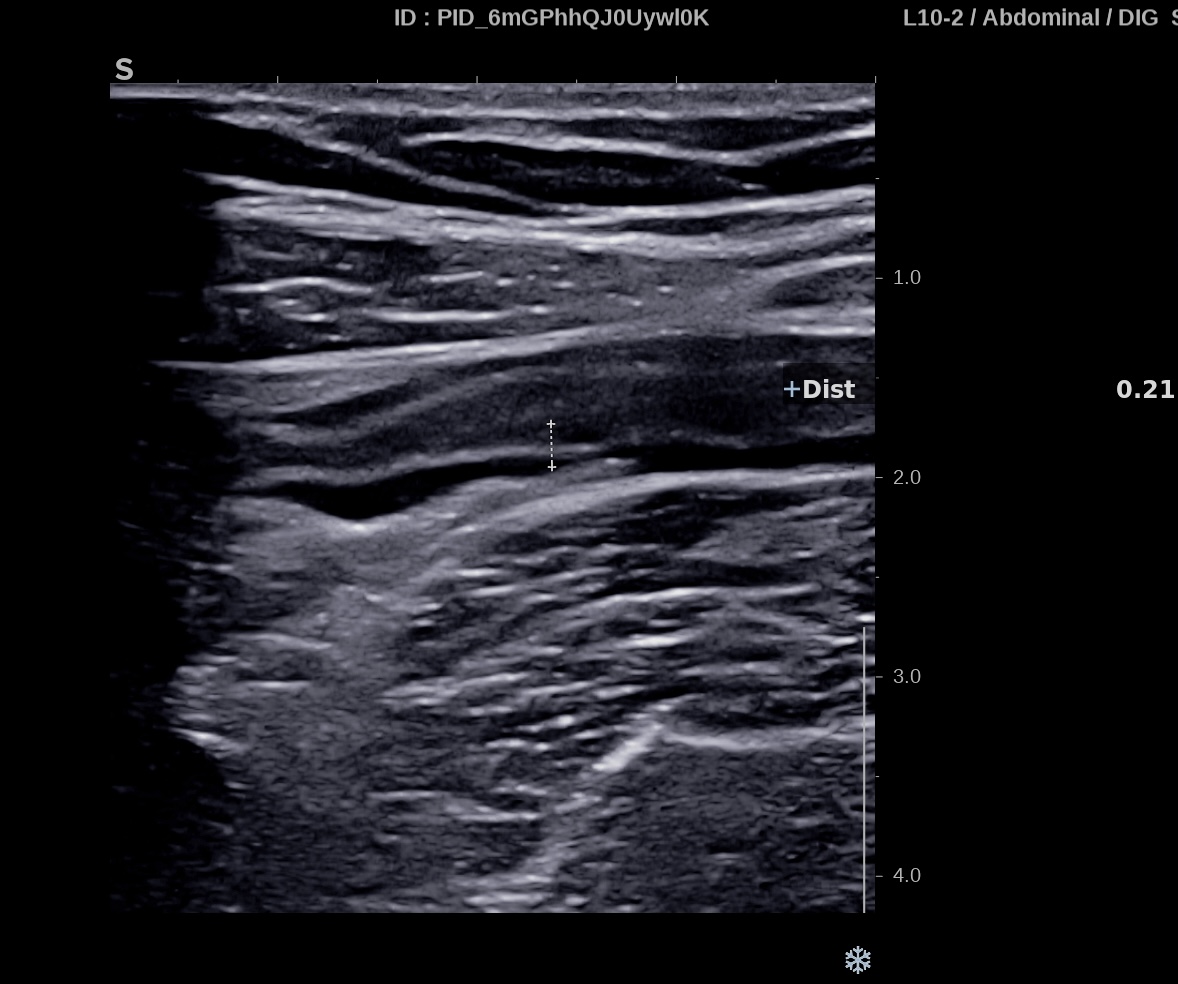

Dès J7 l’amélioration échographique de la paroi se poursuit. L’épaisseur pariétale approche la normale (3 mm) et par endroit 2,1 mm, les couches sont bien visibles, le doppler reste intense (Limberg 3) .

le score de Milan, segment le plus atteint est de (3 x1,4 +2) MUC = 6,2

La paroi est redevenue strictement normale, rien ne permet de la différentier d’un colon sain.

L’épaisseur pariétale est de 1,8 mm, structure en couche totalement rétablie, le Doppler est négatif, Limberg 0.

On retrouve les haustrations coliques normales.

Le score de Milan est de (1,8 x1,4+0) MUC = 2,52